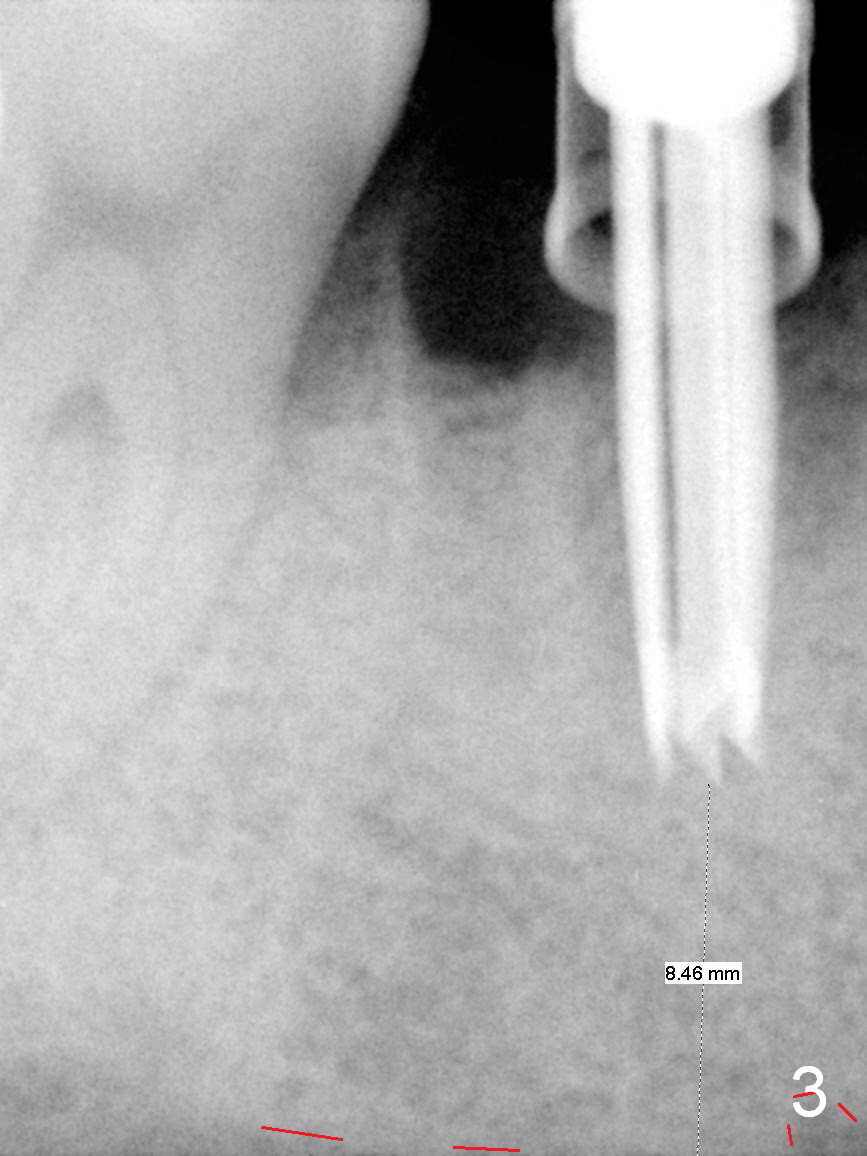

After cleaning the root surface with a surgical curette, a 1.6 mm pilot drill is used to start osteotomy (O) between the mesial (M) and distal (D) roots, followed by a marking bur and 3.8 mm Magic drill 13 mm deep (Fig.1,2). Following root removal, the 3.8 mm drill is reused for 11 mm (Fig.3). After deepening the osteotomy for another 2 mm, a 4.5x13 mm implant is placed with insertion torque of 50 Ncm, followed by allograft (*, .5-2 mm) and a 5x4(2) mm abutment (Fig.4,5). An immediate provisional is fabricated to close the socket (Fig.6 P (lock in)). The detached buccal gingiva (Fig.6 *) is kept in place by applying periodontal dressing (Fig.7 *). Red dashed lines in Fig.1, 3, 5 represents the superior border of the Inferior Alveolar Canal and Mental Foramen.